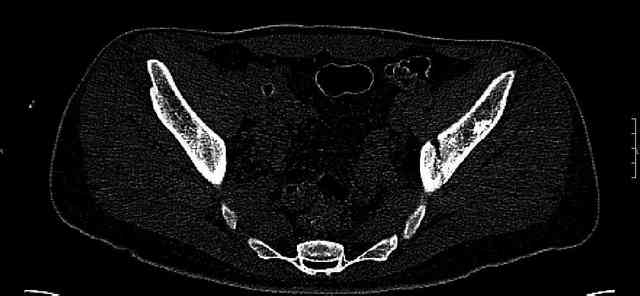

Some more images. Does it help to guess which part of the acetabulum is displaced?

Normal appearing SI joints and a healed posterior column limb... my bet's on caudal segment displacement.